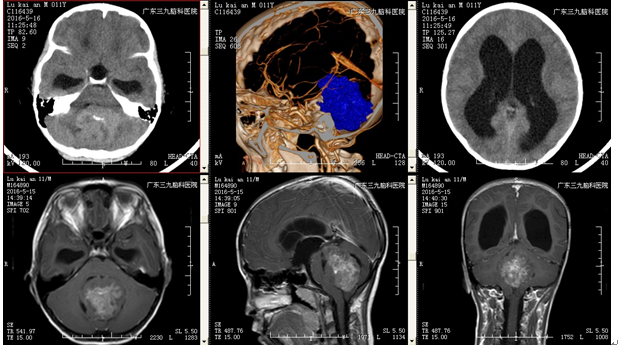

卢某某,男,11岁5月,因行走不稳伴视物不清2月余于2016-05入院。入院时视力:右眼:0.3,左眼:0.8,水平眼颤,行走不稳共济失调,四肢肌力5级,肌张力正常,生理反射存在,病理征阴性。辅助检查:外院头颅CT示:四脑室占位性病变;脑积水;慢性枕骨大孔疝。

治疗前检查

治疗:入院后予完善相关检查,查头颅CTA及MRI示:1.四脑室占位性病变;2.梗阻性脑积水;3.慢性枕骨大孔疝。在全麻下行四脑室肿瘤切除术,术程顺利,术后复查头颅CT、MRI示:呈术后改变,肿瘤全切除,幕上脑室系统扩大较前有所减轻。术后病理结果回报:中枢神经细胞瘤(WHOII级)。出院情况:患者一般情况可,无诉头晕头痛,无呕吐以及肢体抽搐等不适;查体:神志清楚,正确对答以及遵嘱活动,双侧瞳孔等圆等大,对光反射灵敏,颈无抵抗,手术切口I/甲愈合,四肢肌力5级,肌张力正常,生理反射存在,病理征未引出。